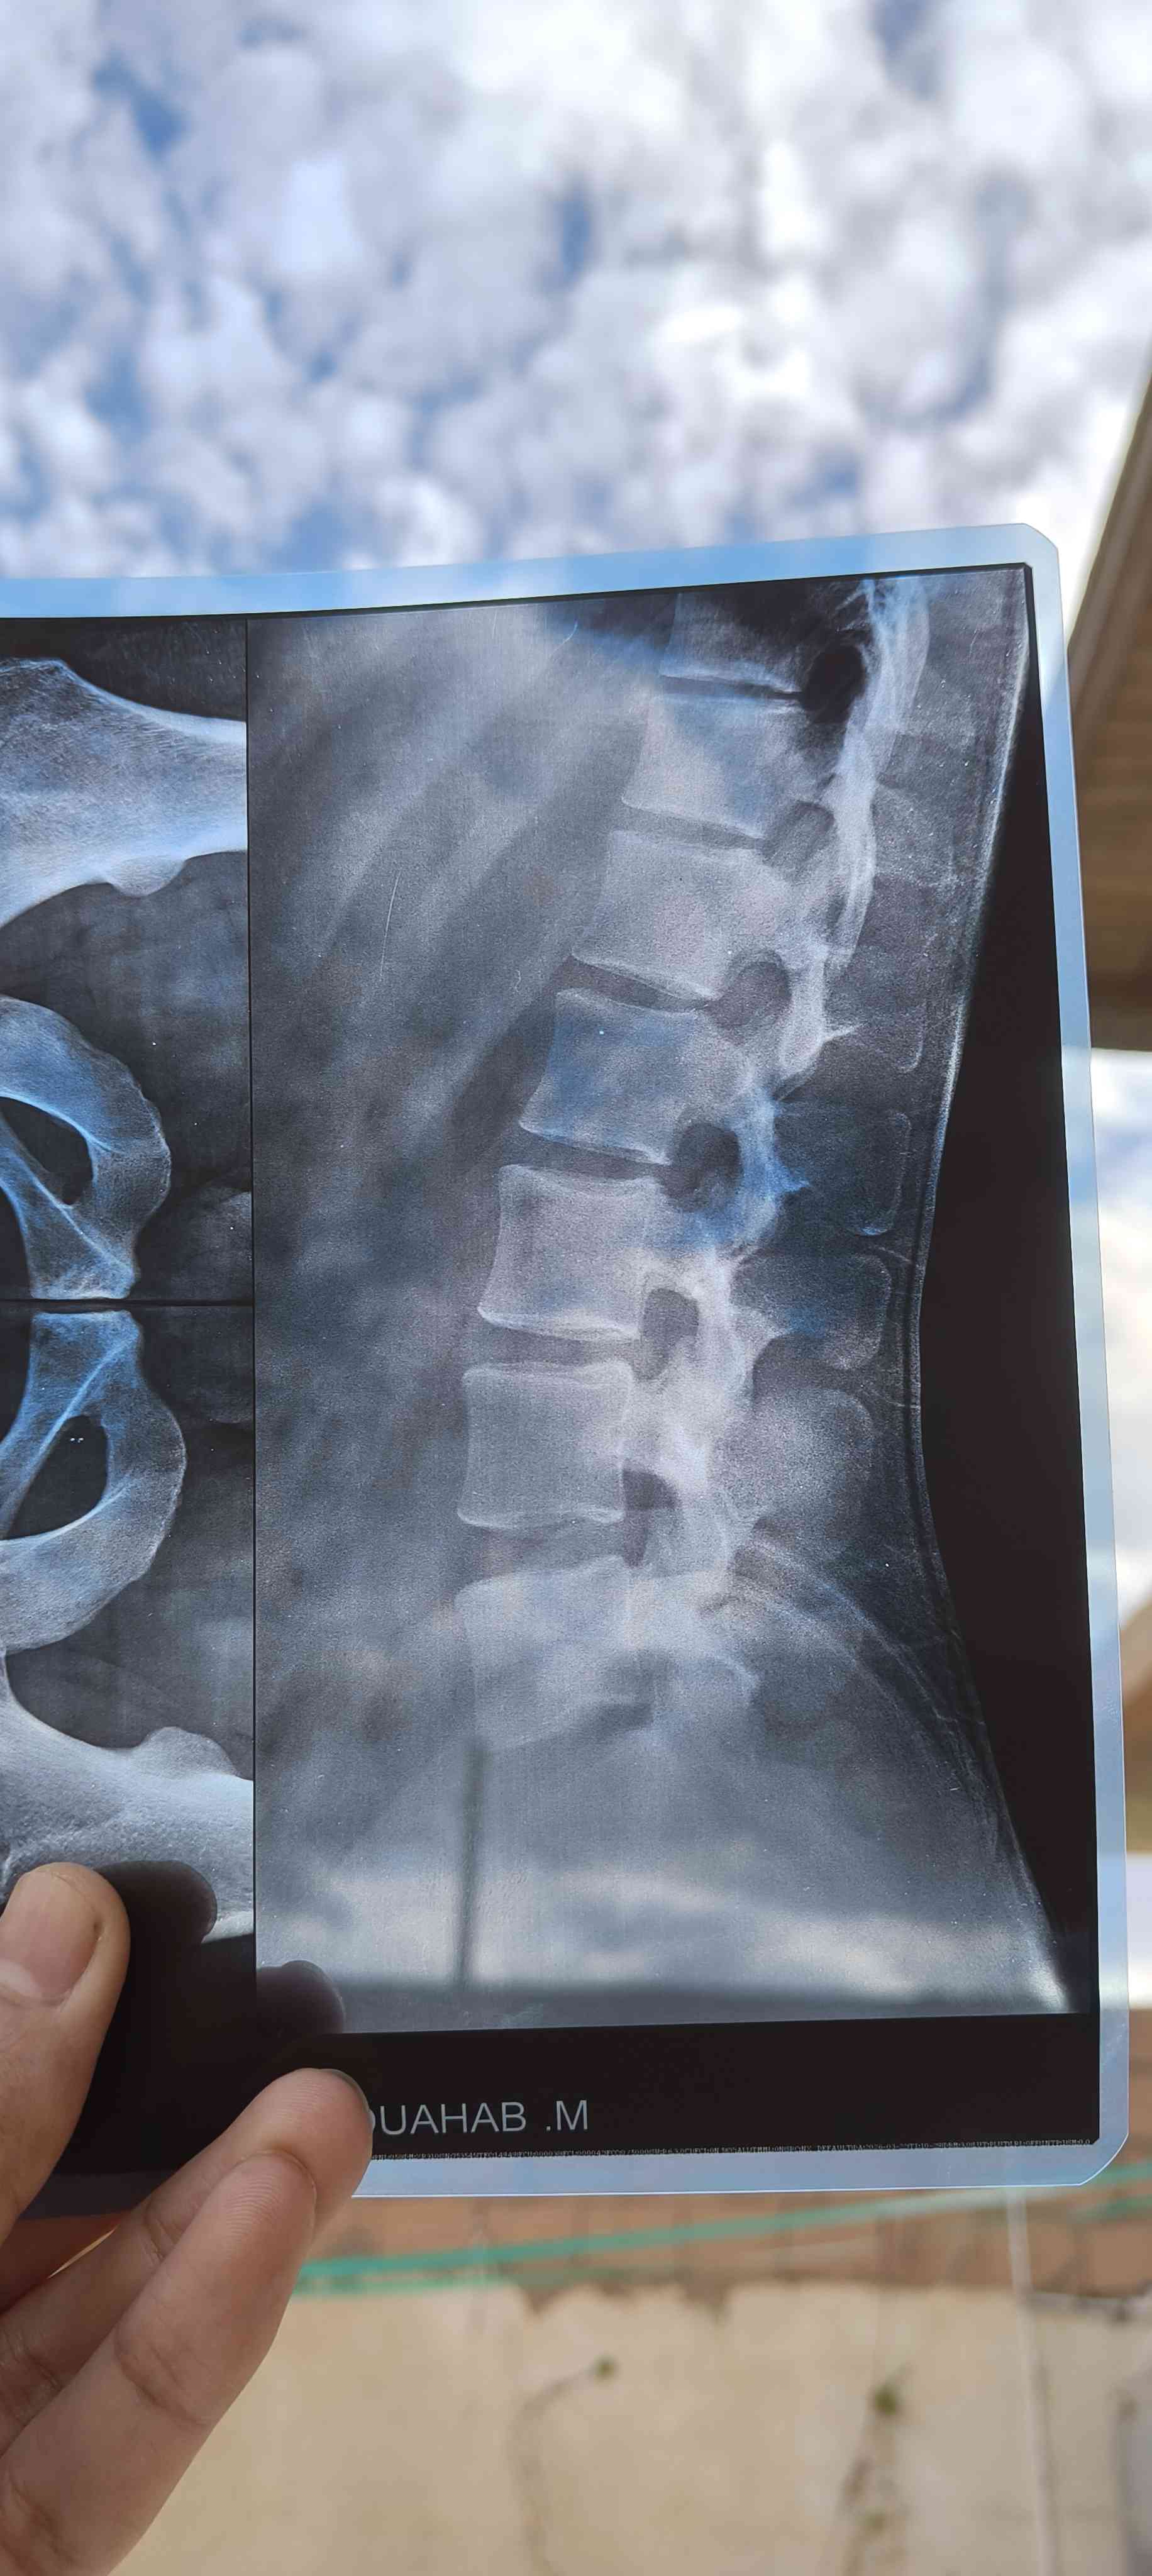

هل حالتي تاكل غضروف الفقرة L5 S1 بتتعالج لدي ألم جانب اليمين في الورك يمتد لأسفل الساق وأسفل الظهر

هذه لاتكفي للتشخيص وممكن تحتاج لرنين --الفحص السريري مهم عليك مراجعة طبيب روماتيزم لاجراء اللازم من تصوير وتحليل للدم مثلا CBC ESR CRP ومعرفة وظائف الاعضاء واليك بعض من النصائح الطبيبه في حياتك اليوميه -وساده سمكها 8-12 سم صلبه نوعا ما والحذر عند استخدام الجوال عدم الانحناء عدم رفع الاشياء الثقيله والنوم والجلوس الصحي والوقوف يكون بتباعد القدمين او رفع احدهم على مرتفع كلوح او طوبه الخ وعند تناول اي جسم يكون بثني الركبتين وممكن العلاج الطبيعي حسب ما يراه 1 2026-03-28T07:42:50+00:00 2026-03-28T07:42:50+00:00

هذه لاتكفي للتشخيص وممكن تحتاج لرنين --الفحص السريري مهم عليك مراجعة طبيب روماتيزم لاجراء اللازم من تصوير وتحليل للدم مثلا CBC ESR CRP ومعرفة وظائف الاعضاء واليك بعض من النصائح الطبيبه في حياتك اليوميه -وساده سمكها 8-12 سم صلبه نوعا ما والحذر عند استخدام الجوال عدم الانحناء عدم رفع الاشياء الثقيله والنوم والجلوس الصحي والوقوف يكون بتباعد القدمين او رفع احدهم على مرتفع كلوح او طوبه الخ وعند تناول اي جسم يكون بثني الركبتين وممكن العلاج الطبيعي حسب ما يراه